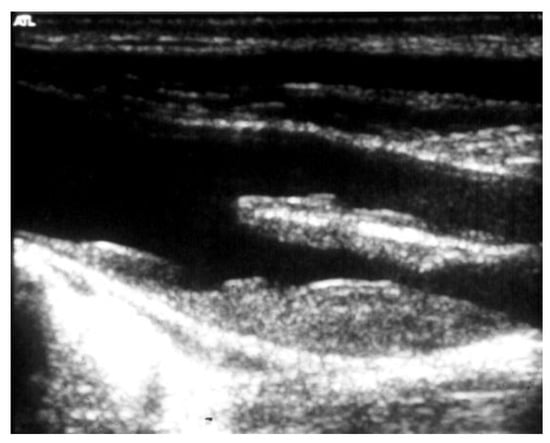

Figure 6. Duplex scan (long axis view) of the extracranial carotid bifurcation, clearly showing an atherosclerotic plaque causing stenosis of the internal carotid artery.

The risk of stroke increases according to the degree of EICS: those greater than 80% carry an annual risk of 4.8% [29]. Duplex scan is a first-level investigation to determine the degree of EICS utilizing peak systolic velocity (Figure 6).

In complex duplex visualization, as in the presence of a highly calcific carotid plaque causing an ultrasound shadow cone, the exact degree of EICS can be accurately measured by computed tomographic angiography (CTA), or eventually by digital subtraction angiography (DSA). Compared to the latter, CTA tends to underestimate the higher and moderate grade EICS [41]. Magnetic resonance angiography (MRA) represents another second-level instrumental examination in patients contraindicated to iodine-based contrast. MRA underestimates EICS since it is not as sensitive to calcification. On the other hand, gadolinium contrast-enhanced MRA can overestimate EICS since it is more impacted by artifacts [42]. Either the NASCET criteria or European Carotid Surgery Trialists (ECST) criteria are used to calculate EICS (Figure 7) [43].